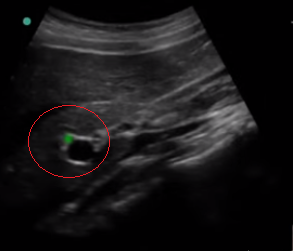

Gallbladder Common Bile Duct (CBD) Image

Highlighted Area: Common Bile Duct (CBD)